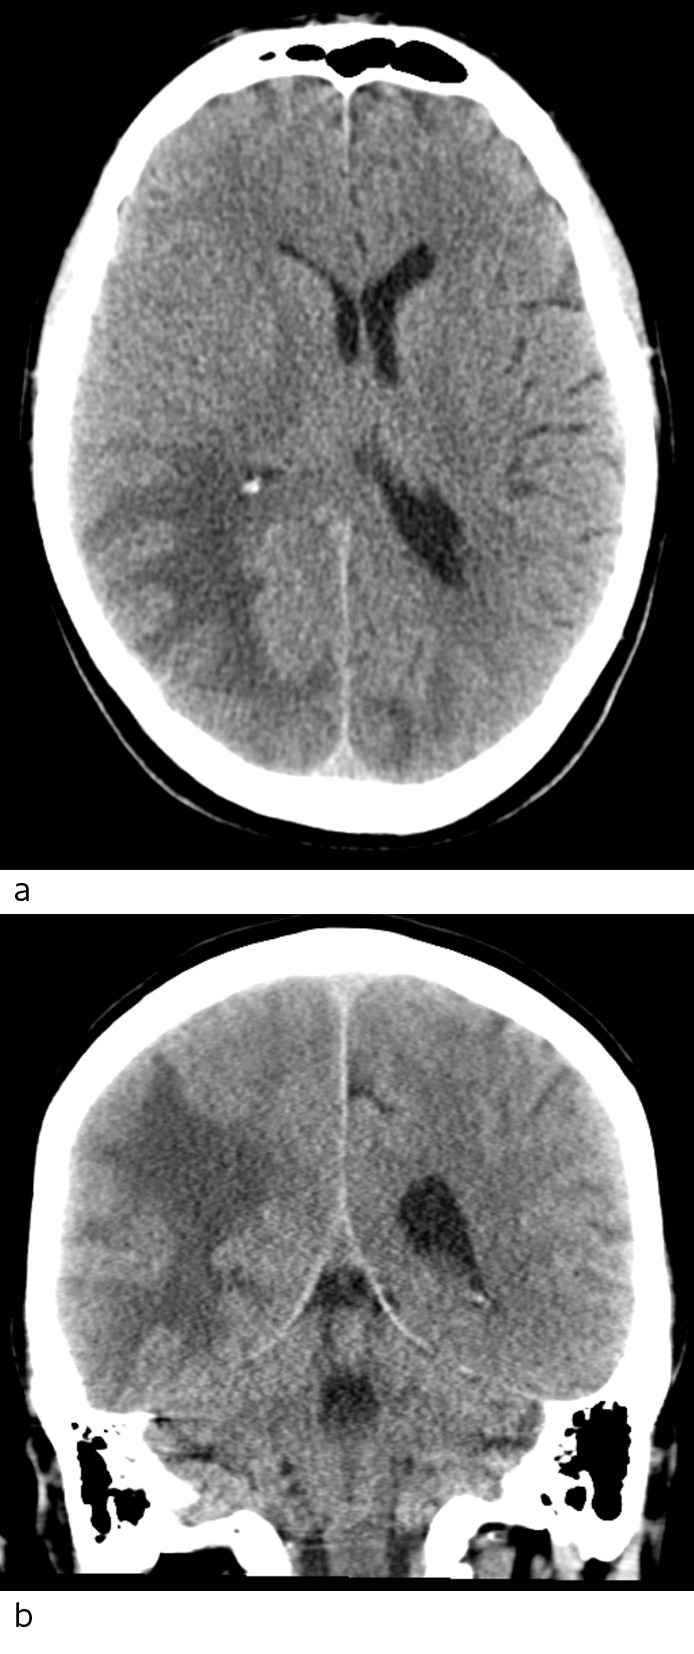

Pasienten ble undersøkt med CT caput uten og med intravenøs kontrast. Det ble sett lavattenuasjon, som ved ødem i hvit substans oksipitalt, mest uttalt på høyre side med masseeffekt og midtlinjeforskyvning mot venstre (fig 1).

Ved øyelegeundersøkelse ble det konkludert med homonym kvadrantanopsi (synsfeltsutfall i begge nedre venstre kvadranter), ellers normale funn. På bakgrunn av uttalte trykksymptomer og påvist hjerneødem på CT mistenkte man primært hjernemetastaser, og det ble derfor startet behandling med høydose perorale kortikosteroider. Pasienten ble henvist til MR caput grunnet fortsatt mistanke om hjernemetastaser.